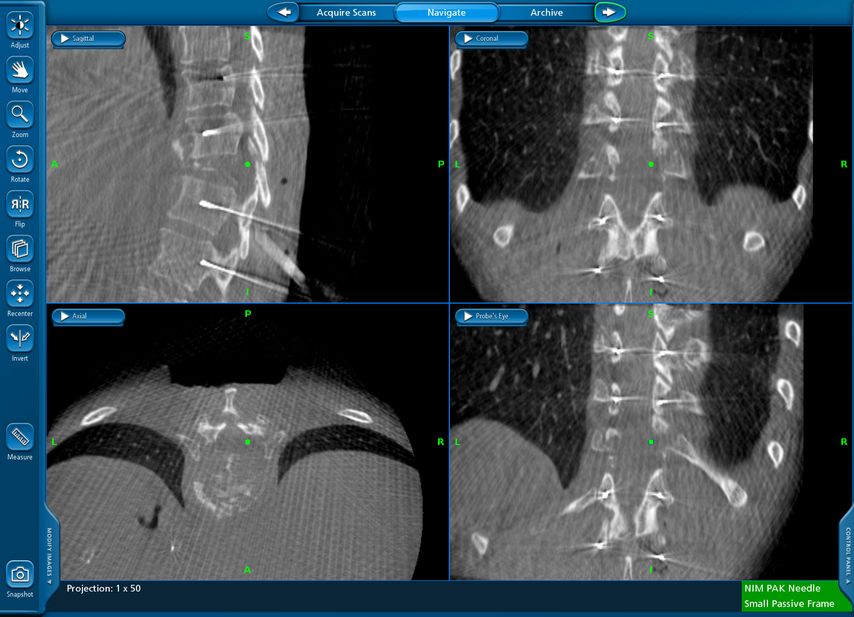

Navigierte Implantation eines „interbody device“ über lateralen Zugang (XLIF; „Xtreme lateral interbody fusion“). Bei der 79-jährigen Patienten kam es nach Fusion L4/5 vor mehr als 10 Jahren zu einer symptomatischen Anschlusssegmentdegeneration L3/4 mit Schmerzen im Dermatom L4 beidseits sowie zu Lumbago. Es erfolgte navigiert die Implantation eines Zugangs in Rechtsseitenlage. Intraoperativ wurde die Referenz am Beckenkamm platziert (Abb. 12) und mit intraoperativem CT (O-Arm) ein 3D-Datensatz gewonnen. Anhand dessen können Instrumente wie Küretten oder Raspatorium (Abb. 13) wie auch die Implantation des Cages selbst (Abb. 14) navigiert werden. Das postoperative Röntgen zeigt einen regelrechten Implantatsitz (Abb. 15).